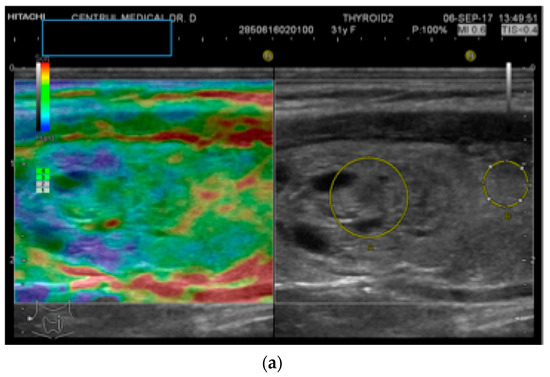

2.2. Elastography Measurements

- Stoian, D.; Timar, B.; Derban, M.; Pantea, S.; Varcus, F.; Craina, M.; Craciunescu, M. Thyroid Imaging Reporting and Data System (TI-RADS): The impact of quantitative strain elastography for better stratification of cancer risks. Med. Ultrason. 2015, 17, 327–332. [Google Scholar] [CrossRef]

- Stoian, D.; Borcan, F.; Petre, I.; Mozos, I.; Varcus, F.; Ivan, V.; Cioca, A.; Apostol, A.; Dehelean, C.A. Strain elastography as a valuable diagnosis tool in intermediate cytology (Bethesda III) thyroid nodules. Diagnostics 2019, 9, 119. [Google Scholar] [CrossRef]